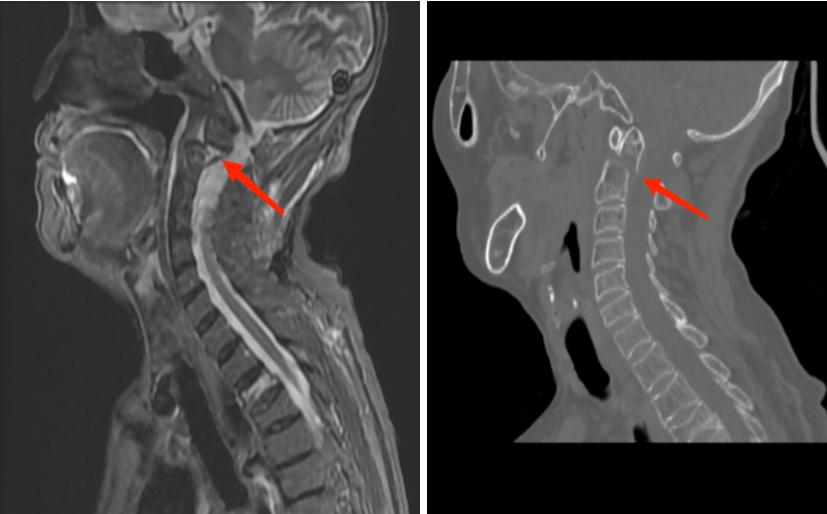

患者,许奶奶,入院前一天在砍柴时不慎摔倒,伤后头颈部疼痛明显,颈部活动受限,伴头晕、恶心、干呕及上肢麻木等症状,在家观察无缓解后由家人护送至南江县人民医院骨科就诊。入院后,骨科医师张鹏十分重视患者的病情,在医技科室的协助下迅速完善了辅助检查,科主任杨涛及时组织开展了病例讨论及术前远程会诊,明确了该患者为枢椎齿状突Ⅱ型骨折,确定了手术方案为经后路枢椎齿突骨折并寰枢椎脱位切开复位椎弓椎螺钉内固定术+寰枢关节植骨融合术。

图为术前CT显示